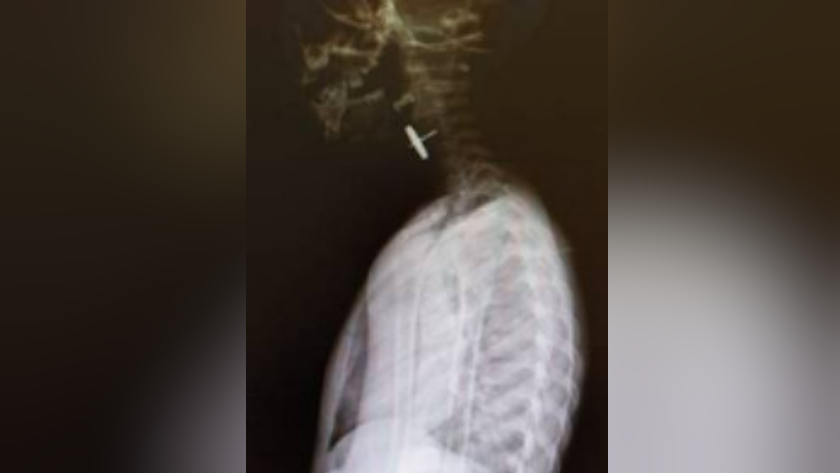

Металлическая деталь от игрушки застряла в пищеводе ребенка и грозила серьезными осложнениями. Для оказания помощи необходимого уровня трехлетнего мальчика доставили из пгт Магдагачи в детскую областную больницу санавиацией.

Дорога в сопровождении медицинских специалистов в сложных погодных условиях заняла пять часов. Конструкцию со штырем длиной полтора сантиметра успешно извлекли. Сейчас пациент вместе с мамой уже выписаны из больницы, сообщает Минздрав Приамурья. Отмечается, что за прошлую неделю представители областного центра Медицины катастроф с помощью воздушного и наземного транспорта эвакуировали из одной больницы в другую 27 человек, в том числе восьмерых детей. В основном это были пациенты с сердечно-сосудистыми проблемами, одного из них отправили в специализированный центр в Хабаровск.